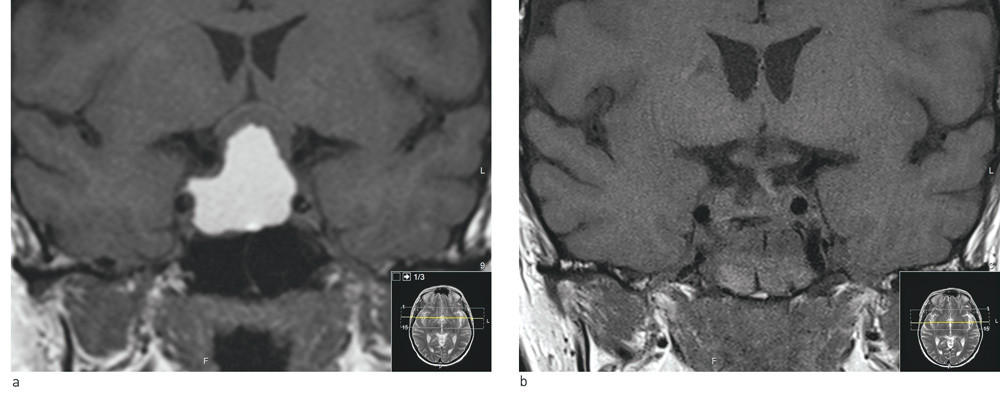

An MRI scan of the pituitary gland (Fig. 1a) revealed a large (31 mm × 29 mm × 26 mm) cystic intracellular tumour, with a large supracellular component that raised the optic nerve decussation. The finding was assumed to represent either a craniopharyngioma or a cystic pituitary macroadenoma.

Figure 1  Coronary T1-weighted MRI images without contrast. a) Large opacity in sella turcica that extends up in the…

Figure 1 Coronary T1-weighted MRI images without contrast. a) Large opacity in sella turcica that extends up in the suprasella direction. The optic nerves and optic nerve decussations have been pushed upwards and are seen as a thin, half-moon shaped strip above the tumour. The tumour has a solid component with a low signal just under the optic paths. The large cystic component is seen with a high signal and parallels the internal carotid artery bilaterally. b) Post-operative status. Tumour was removed transphenoidally. There are copious blood products in the sphenoidal sinus. The optic nerves and optic nerve decussations are now lying free and their thickness has normalised. Under them the pituitary stalk is seen in the mid-line with a slight deviation to the left (right in the picture)